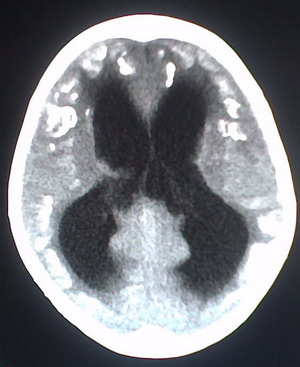

以下是引用jiajie在2009-2-3 20:02:00的发言:[br]脑室周围白质区可见大量斑片状钙化,部分融合成带状,双侧侧脑室及第三脑室扩大。[br]考虑弓形体原虫感染。(先天性宫内感染、torch综合症)

以下是引用lkc8963在2009-2-3 21:15:00的发言:[br]临床眼睑可见静脉扩张,ct双侧眼上静脉亦示扩张,颅内钙化以皮层\\软脑膜为主而不是位于白质和室管膜,再加上静脉窦异常,还是应该考虑静脉血管瘤病,可能为较复杂的血管畸形.

以下是引用卜一在2009-2-4 9:21:00的发言:[br]sturge-weber综合征:面部三叉神经分布区的毛细血管性或海绵状血管瘤以及同侧枕、顶或额叶软脑膜的血管瘤(以静脉性为主)。脑皮质,特别是第二三层,毛细血管可有增厚和钙化。局部发生层状坏死、神经细胞脱失、萎缩、胶质细胞增生及钙盐沉着。可根据面部典型分布的特征性皮痣作出诊断。头颅ct:发现面部血管瘤同侧的脑内病理钙化影,呈双层线条波浪形、脑回形或树枝形。本例支持:sturge-weber综合征![br]